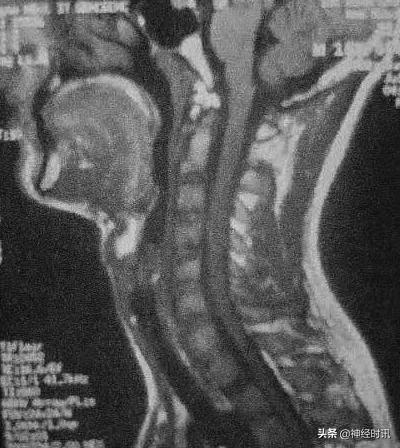

颈椎MRI(2011年10月):C2~C4可见脊髓肿胀,其内可见稍长T1,长T2信号影,无强化。

临床诊断上,除了McDonald2010年诊断标准(现已更新至McDonald2017年诊断标准)外,MRI也具有十分重要的重要。结合上述病例,该患者头部MRI中有多发的白质部分病灶,颈部MRI中可见单个椭圆形病灶,边界清楚。